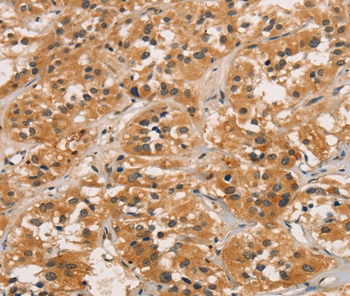

Immunohistochemical analysis of paraffin-embedded Human thyroid cancer tissue using #36377 at dilution 1/30.